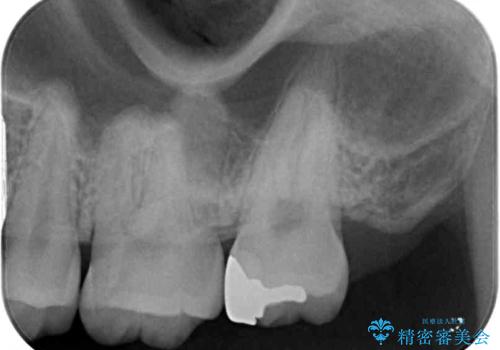

レントゲン写真より、1番奥の歯に虫歯があることが分かりました。

奥で目立たないことから、虫歯の再発リスクが最も低く、咬合力による歯への負担も少ないゴールドインレー(PGAインレー、白金加金インレー)にて修復治療をすることとしました。